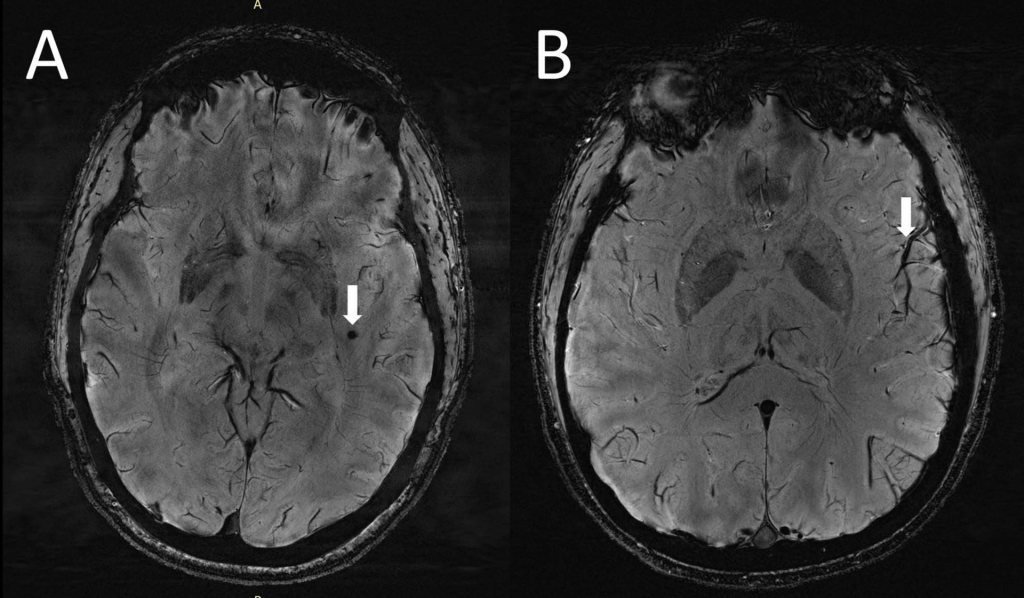

研究小组使用ultra-high-field 7 t MRI研究偏头痛和扩大血管周的空间之间的联系。

结果表明,在椎体的数量扩大血管周的空间semiovale,白质的中心区域,在偏头痛患者大大高于健康对照组。

“我们研究了慢性偏头痛和情景性先兆型偏头痛,发现,这两种类型的偏头痛,血管周的空间更大的中枢semiovale,”徐说。